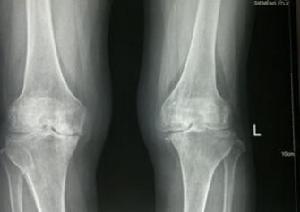

膝關節骨性關節炎是指由於膝關節軟骨變性、骨質增生而引起的一種慢性骨關節疾患,主要表現是關節疼痛和活動不靈活,X線表現關節間隙變窄,軟骨下骨質緻密,骨小梁斷裂,有硬化和囊性變。又稱為膝關節增生性關節炎、退行性關節炎及骨性關節病等。本病多發生於中老年人,也可發生於青年人,可單側發病,也可雙側發病。

5.膝關節正、側位X照片,顯示髕骨、股骨髁、脛骨平台關節緣呈唇樣骨質增生,脛骨髁間隆突變尖,關節間隙變窄,軟骨下骨質緻密,有時可見關節內游離體。